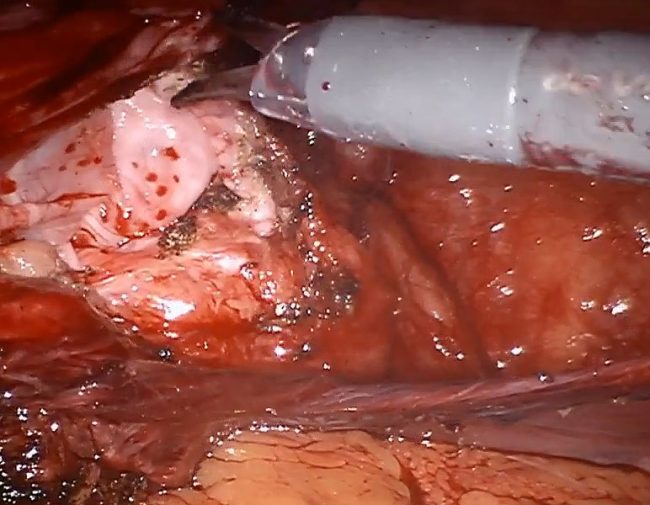

Robotic assisted repair of recurrent right inguinal hernia with mesh

This is a 52 year old male with history of right inguinal hernia repair 10 years ago who presented with a painful bulge in the right groin. Patient underwent a robotic assisted repair of recurrent right inguinal hernia with mesh. There was an evidence of recurrent right inguinal hernia on the most medial aspect of the pervious hernia repair with incarcerated pre-peritoneal fat in the hernia defect.